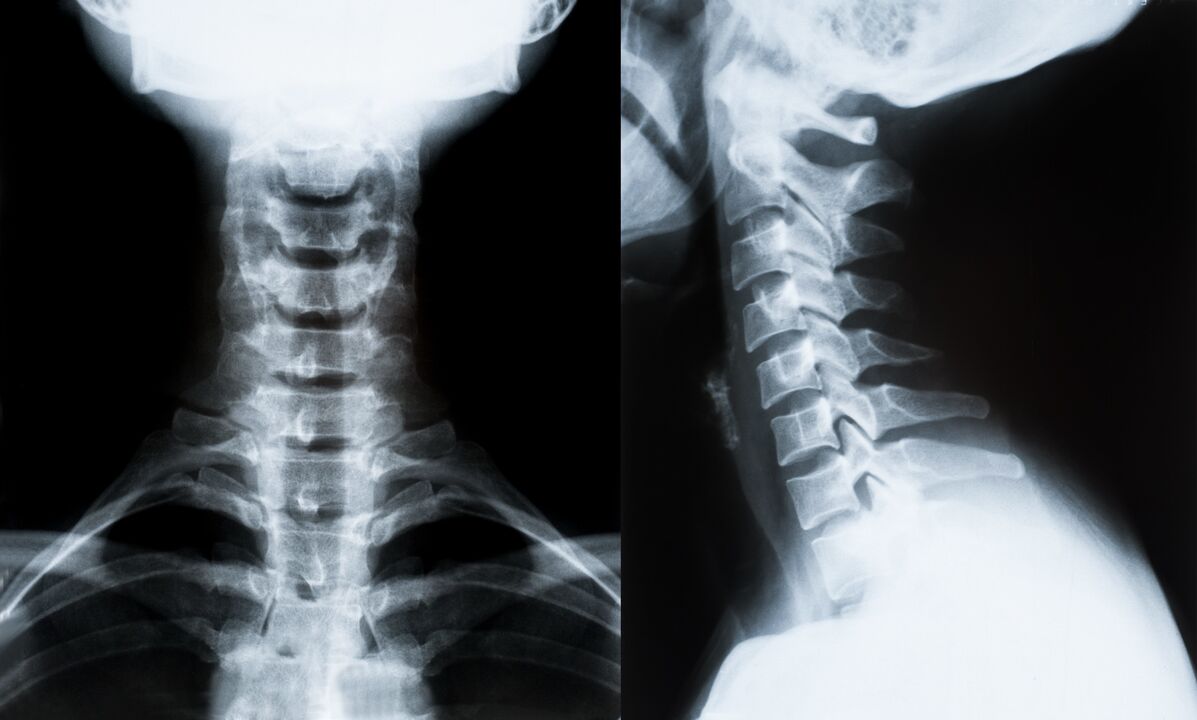

Servikal omurganın osteokondrozu için ana tanı yöntemleri ve tedavinin daha da belirlenmesi:

- Röntgen. En az etkili ancak geleneksel teşhis yöntemi.

- Manyetik rezonans görüntüleme en etkili tanı yöntemidir. Hastanın bu şekilde muayenesi ile gerekli tüm yapılar görünür hale gelir.

- Değişikliklerin ölçülmesi gerekiyorsa bilgisayarlı tomografi kullanılır. Fıtık ve diğer şeylerin varlığını belirler.

- Son yöntem ultrason dubleks taramadır. Bu araştırma yöntemi, arterlerdeki kan akış hızını belirler.